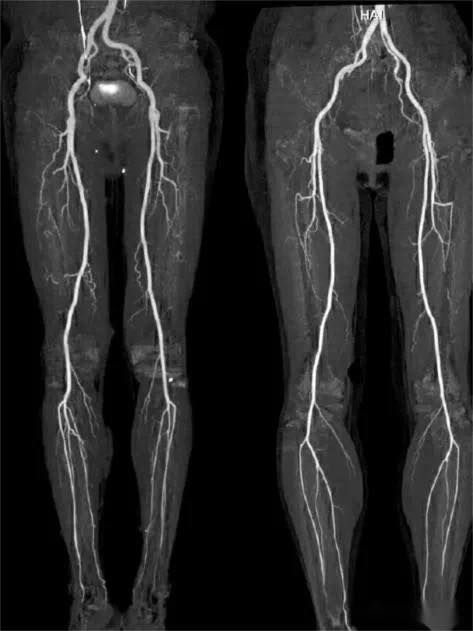

فحص CTA للشرايين الطرفية السفلية

فحص CTA للشرايين الطرفية السفلية – دليل توعوي وإرشادي

‏CTA هو اختصار لـ Computed Tomography Angiography، أي التصوير المقطعي المحوسب للشرايين باستخدام الأشعة المقطعية مع حقن مادة تباين (صبغة) لتصوير الشرايين بدقة عالية.

ويُعد وسيلة أساسية لتقييم أمراض مثل تصلب الشرايين، القدم السكري، والجلطات الدموية الطرفية، إضافةً إلى دوره في التخطيط قبل العمليات الجراحية أو التداخلات الوعائية.